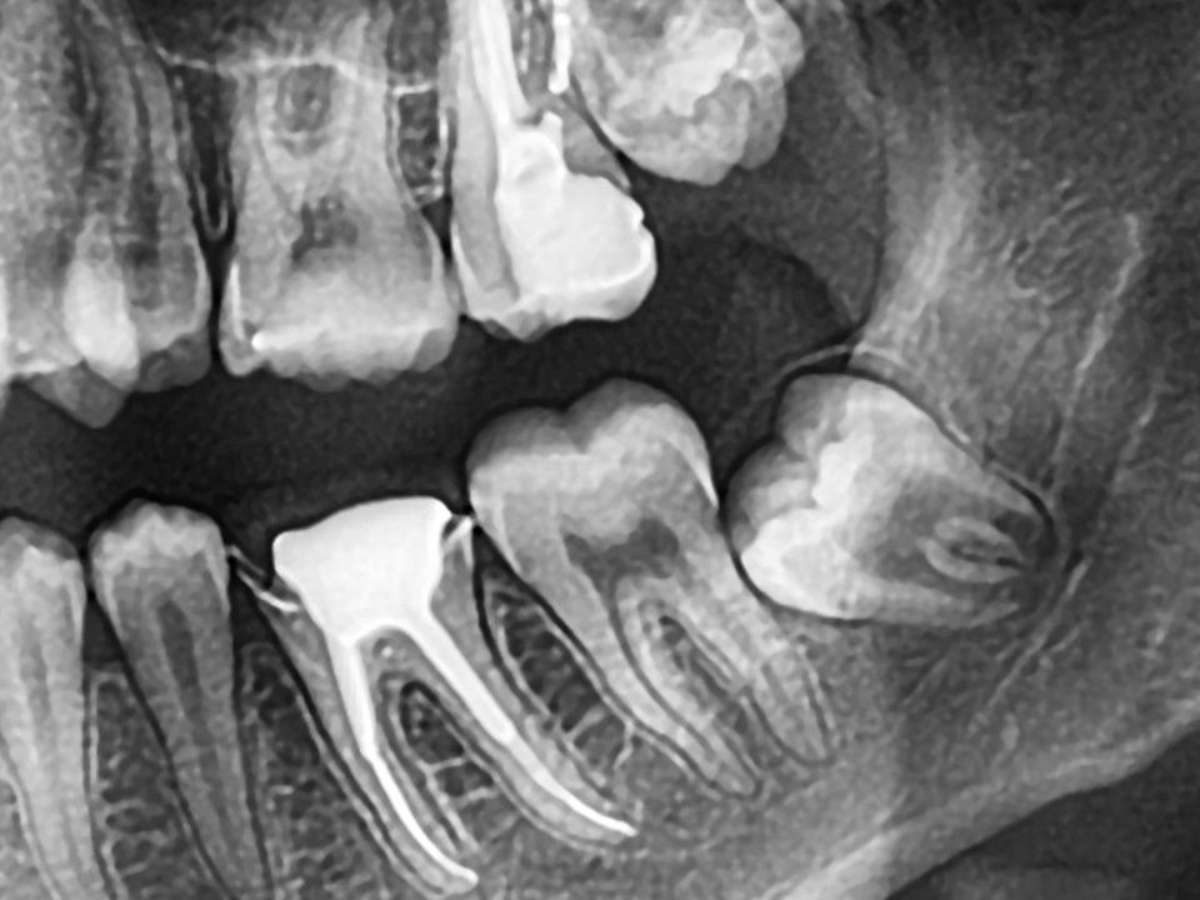

Na maioria das vezes, o siso fica sem espaço para erupcionar e começa a pressionar os dentes vizinhos, alterando o alinhamento do sorriso e causando dor ou inflamação. Em casos em que o dente fica parcialmente exposto (os chamados semi-inclusos), há maior risco de acúmulo de resíduos e infecções. Os sintomas mais comuns incluem dor intensa, inchaço, sensibilidade e até fragilidade óssea. Por isso, a extração costuma ser o tratamento mais indicado.

A cirurgia de remoção do siso é simples, feita com anestesia local e duração média de menos de uma hora. O paciente tem alta no mesmo dia e deve seguir recomendações básicas: repouso, alimentação leve e boa higiene bucal. O ideal é consultar o dentista antes que os sisos causem desconforto. Com exames de imagem, o profissional consegue identificar se o dente está em formação e avaliar o momento certo para agir - muitas vezes, de forma preventiva.